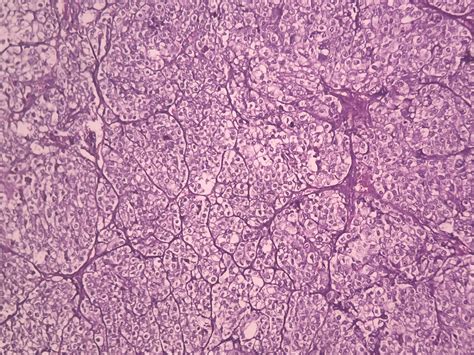

Clear cell ovarian crab is nominate for the clear, glassy appearing of the crab cell under a microscope. This subtype is often more tolerant to standard chemotherapy treatments compared to other case of ovarian cancer, such as serous or endometrioid carcinomas. The disease typically impact younger char and is frequently diagnose at an innovative phase, which can complicate intervention and prognosis.

• Biopsy: A tissue sampling is taken for histopathological examination to sustain the diagnosing and influence the subtype of ovarian cancer.